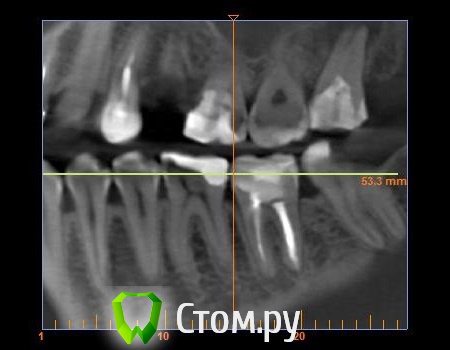

mastermind Опубликовано 22 августа, 2014 Автор Поделиться Опубликовано 22 августа, 2014 Нарезал 3 картинки из КТ Ссылка на комментарий